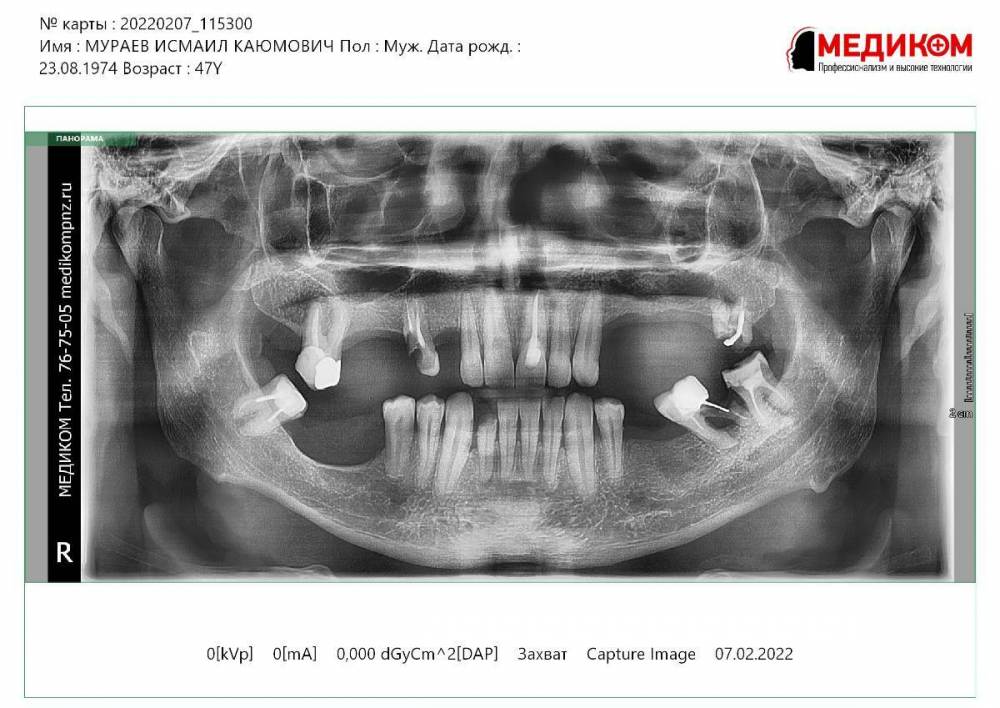

Bibars Опубликовано 16 декабря, 2023 Поделиться Опубликовано 16 декабря, 2023 (изменено) Здравствуйте. Уважаемые доктора, подскажите, пожалуйста. Пациент и. 49 л требуется полная реабилитация. 14, 27, 37, 38, 42, 48 периапикальные изменеия. Хочу сохранить 17, 42. План примерно следующий: установить импланты в области 13, 14,16 24, 25, 28, 35, 37, 38. Не уверен что делать с 4 квадрантом? в голове 2 варианта 1)Подсыпать кость 2) установить коротыши Anyridge . Если есть какие то дополнения, замечания, прошу поправьте . Если нужны еще какие то срезы ССылка на кт https://disk.yandex.ru/d/VS0gWCBpR_Mq9w Изменено 16 декабря, 2023 пользователем Bibars Ссылка на комментарий

Irouil Опубликовано 16 декабря, 2023 Поделиться Опубликовано 16 декабря, 2023 1 прячьте личные данные пациента, он Вам за это спасибо не скажет 2 если Вы всерьёз рассматриваете вариант "подсыпать кость" в таких условиях - точно не подсыпАть 3 для безопасной работы тут нужны импланты 4-4.5 мм, ЕМНИП у эниридж 5.5 мм, так что лучше рассмотреть ТЛ 4 если супракрестальной аугментацией и ТЛ имплантацией не владеете - я бы нашёл доктора, который владеет, договорился бы на референс пациента за право поприсутствовать на операции 1 4 Ссылка на комментарий

Большой Зеленый Опубликовано 19 декабря, 2023 Поделиться Опубликовано 19 декабря, 2023 Однозначно НКР . сетку, Кури, сосиску ,крышку сундука ..любой вариант которым владеете Ссылка на комментарий

Bier Опубликовано 19 декабря, 2023 Поделиться Опубликовано 19 декабря, 2023 а я бы 2 астры по 6мм нашел куда поставить 1 Ссылка на комментарий